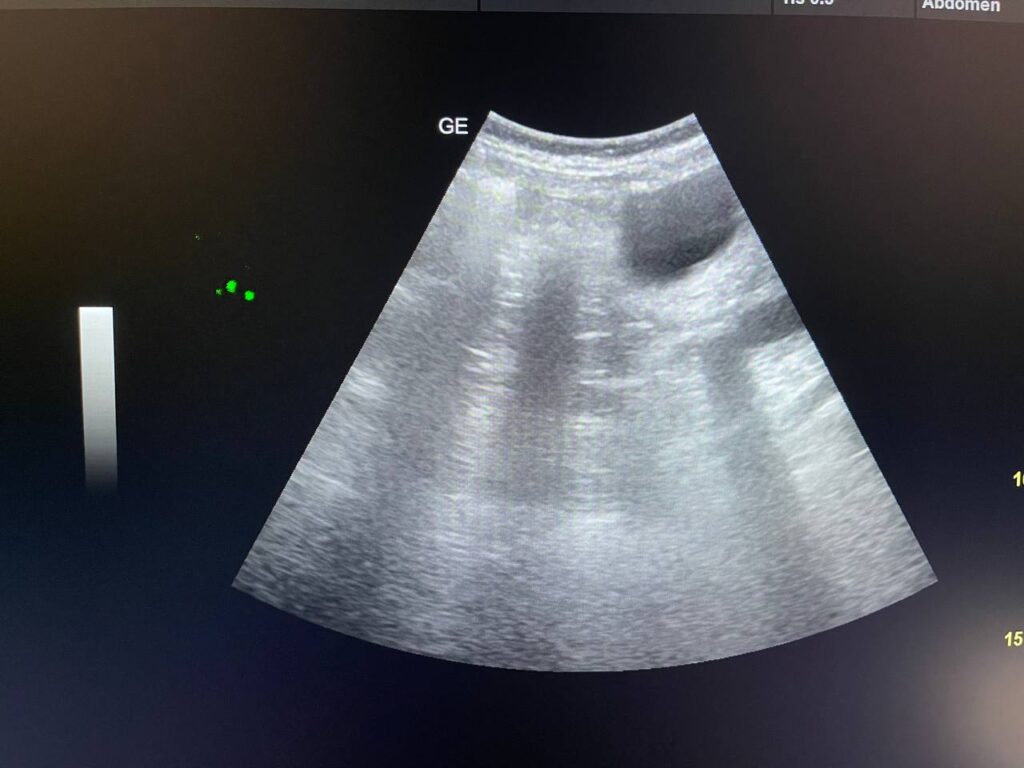

GB STONES & CBD STONE

Gall bladder distended,  increase wall thickness 5.5mm edematous, contain multiple mobile stones of variable sizes , the largest 12mm + dilated common bile duct 13mm , due to presence of stone about 25mm in the distal part